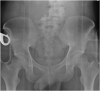

Case presentation: A 26-year-old male who suffered L4-5 fracture dislocation and some hemorrhage in pelvic cavity following a motorcycle accident. He had a median sacral artery injury, and we tried to the trans-catheter arterial embolization, however it could not be success. The embolization was performed using of gelatin sponges in bilateral internal iliac artery and left 4th lumber artery. After his admission, a demand of transfusions lasted for 7 days.